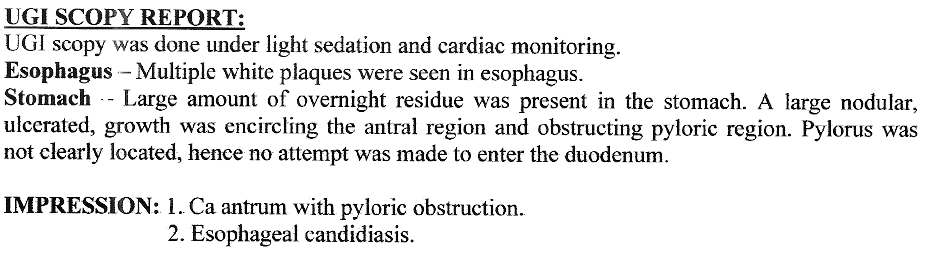

Stomach Outlet Obstruction

Causing Abdominal Fullness and Vomiting

Cancer of the Stomach with Vomiting